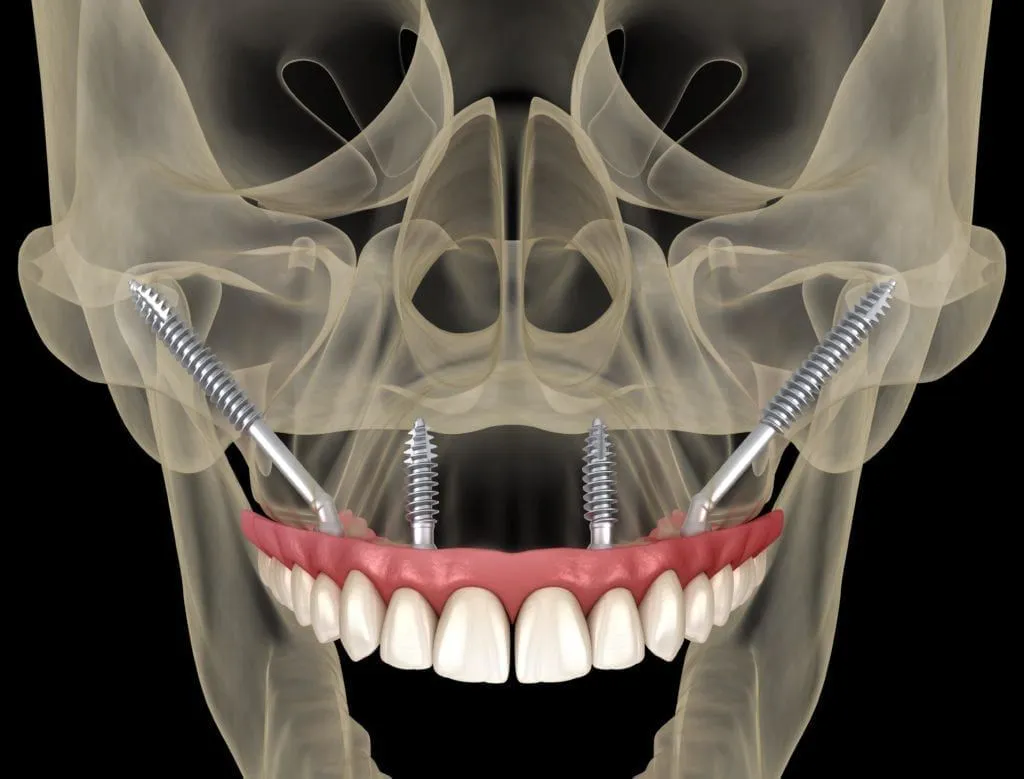

Patients who want dental implants but have extensive bone loss in the upper jaw can benefit from zygomatic (Zygoma) implants. This procedure eliminates the need for bone grafting (bone augmentation). Unlike traditional "root-form" dental implants, which are placed in the jaws to replace teeth, these implants are inserted into the zygomatic bone (cheekbone) to support upper jaw (maxillary) teeth, bridges, and dentures.

Zygoma implants are placed in to the zygomatic bone (cheek bone), which would be denser than the upper jaw. This strong foundation for implant stability distributes stress across a large region, allowing for the successful rapid installation of dental bridges during surgery (no need to use a denture or go without teeth for any period). These implants have been used safely and successfully since the late 1980s.

Zygomatic implants commonly called "Zygoma," traverse into the deficient area of your upper jaw to attach to the bottom of the cheekbones through your sinuses and are an alternative to bone grafting procedures in the upper jaw. These implants are put into the back area of your jaw from within your mouth and can be coupled with one or more standard (root form) implants in the front part of your jaw.

Depending on the requirement of the patients, either two (one on each side) or four (two on each side) implants are put into place to support full or partial dental bridges.